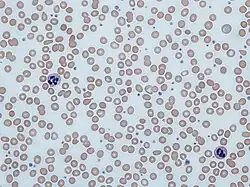

| Blood smear showing iron-deficiency anemia, with small, pale red blood cells | |

Iron-deficiency anemia is the most common type of anemia overall, and it has many causes. RBCs often appear hypochromic (paler than usual) and microcytic (smaller than usual) when viewed with a microscope.